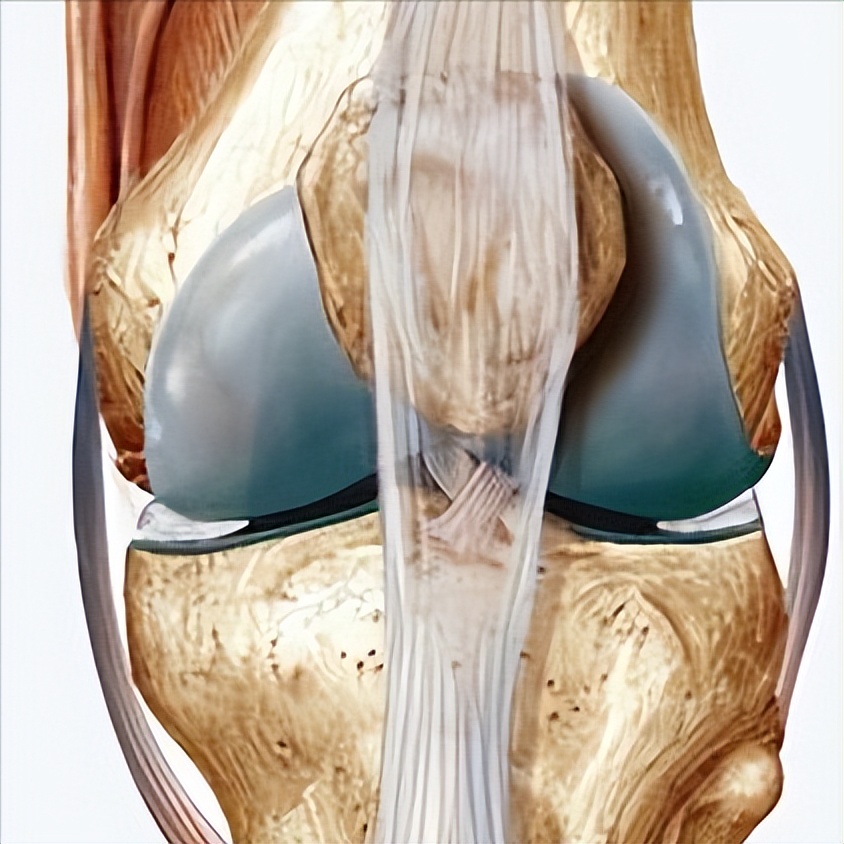

但胫骨结节骨牵引有其特有的并发症:可致胫骨半脱位,膝关节韧带牵拉或损伤胫骨结节,导致胫骨近端骨骺生长阻滞以及后期的反弯畸形 ,还可使伴发于股骨骨折的膝关节韧带或半月板损伤进一步加剧。

因此只有由于骨骼结构或皮肤问题而无法进行股骨远端骨牵引且无膝关节损伤时才行胫骨结节骨牵引。胫腓骨下联合骨牵引于双侧小腿胫腓下联合上方0.5cm处在同一平面避开胫腓骨远端骨骺从外向内进针,将患者双下肢伸膝屈髋90°位悬吊牵引。